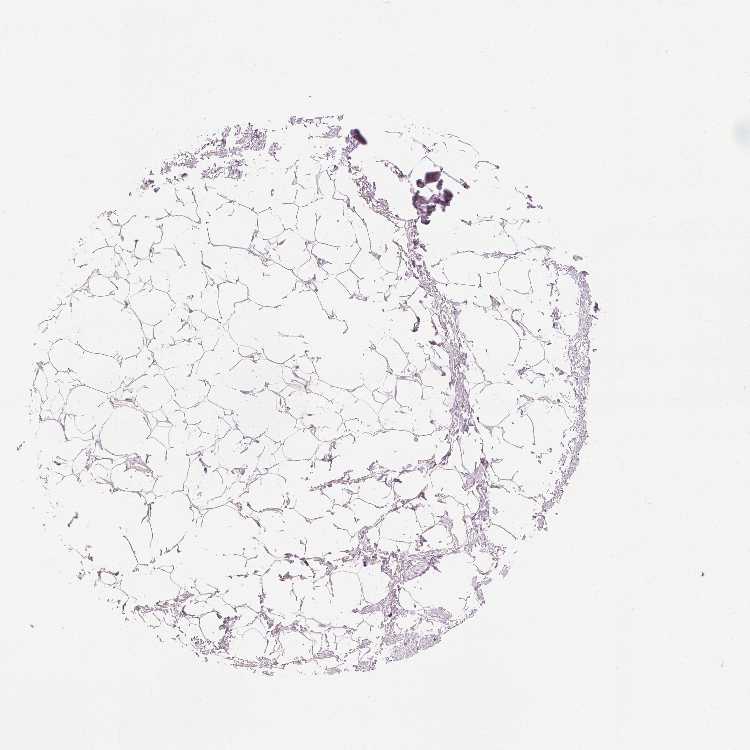

SOFT TISSUE 2 - Antibody stainingi

Antibody staining in the annotated cell types in the current human tissue is reported as not detected, low, medium, or high, based on conventional immunohistochemistry profiling in selected tissues. This score is based on the combination of the staining intensity and fraction of stained cells.

Each image is clickable and will lead to virtual microscopy that enables deeper exploration of all samples and also displays staining intensity scores, fraction scores and subcellular localization as well as patient and tissue information for each sample.

Antibody HPA023099Antibody HPA056734Antibody CAB002138

Fibroblasts Not detectedNot detectedNot detected

Peripheral nerve LowNot detectedNot detected